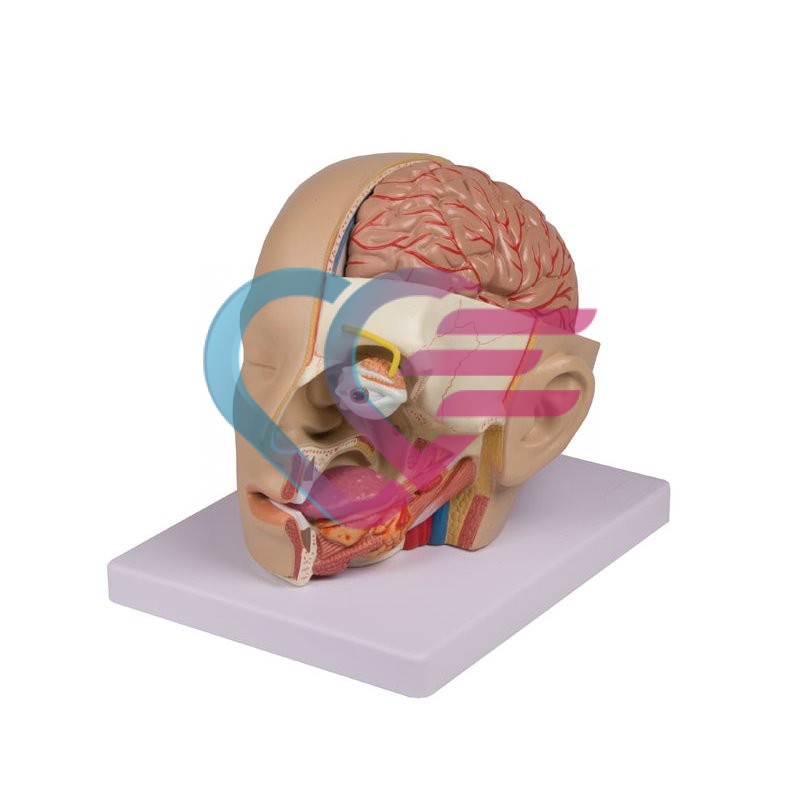

Povezani proizvodi